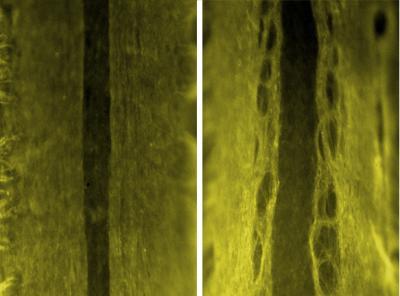

This shows neatly organized axons traveling up and down the spinal cord of a healthy, embryonic mouse (left). Axons in mice without dystroglycan (right) are tangled and disorganized.

(Photo Credit: Kevin Wright)